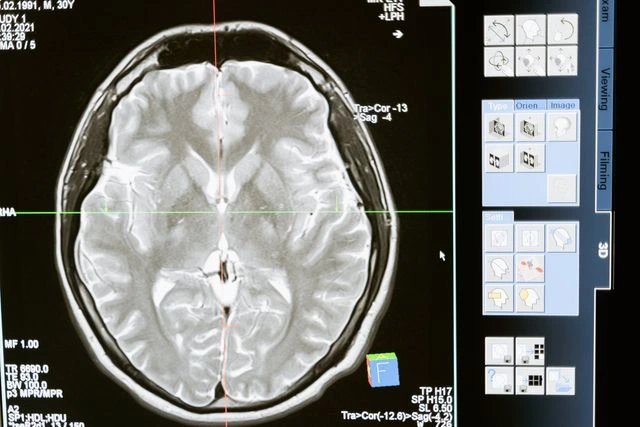

EXPERT DOCTORS AND SURGEONS IN NEW JERSEY FOR: BRAIN, SPINE, NEUROVASCULAR, NEUROLOGY, NEUROPSYCHOLOGY, PAIN, & ORTHOPEDICS

Being diagnosed with a brain, spine, or orthopedic condition can put your life on pause. From the pain of symptoms to the stress of surgery, the New York and New Jersey doctors at IGEA Brain, Spine, Pain & Orthopedics have a deep understanding of the challenges our patients face and provide renowned care that exceeds expectations.